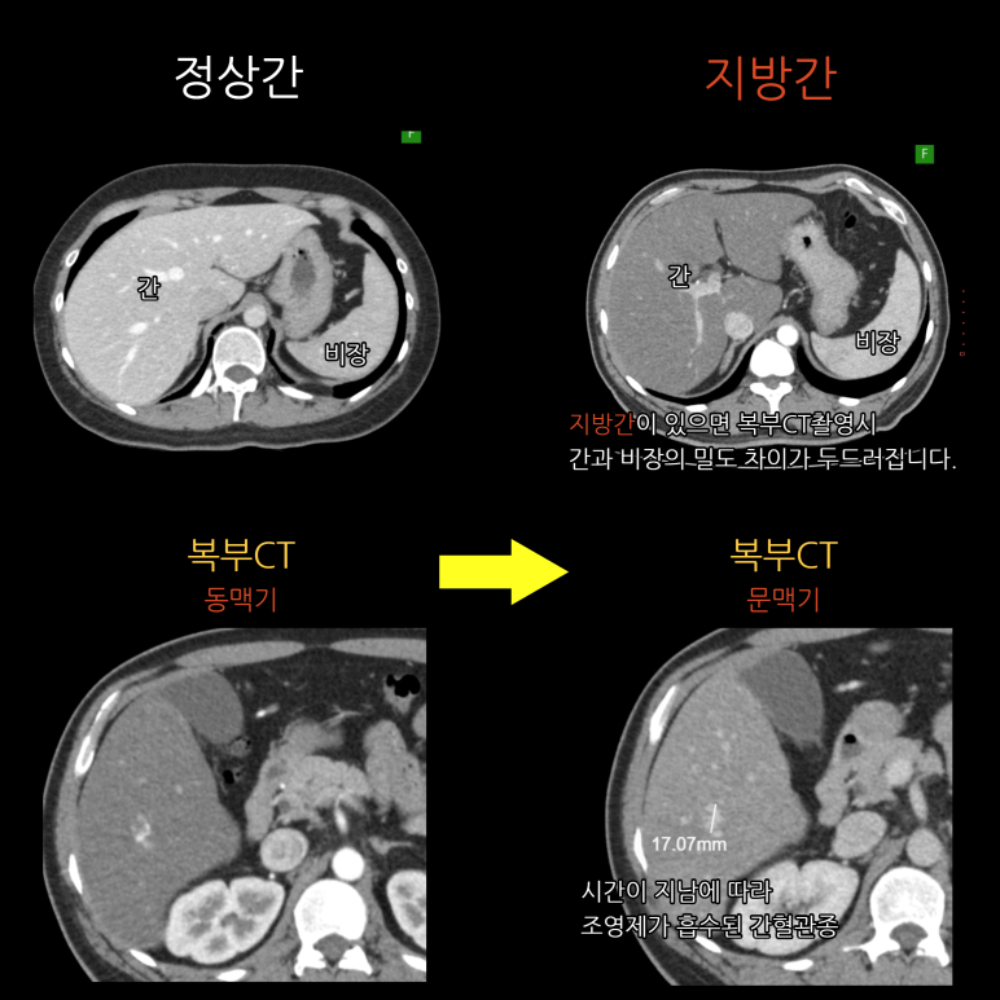

간 실질 전반에 지방간 소견이 보이며, S6 부위에 1.7cm 크기의 혈관종 가능 병변이 관찰됩니다.

지속 추적 시 변화가 없으면 추가 처치 없이 경과 관찰하며, 지방간 개선을 위해 체중 조절·운동·음주 제한을 권합니다.